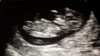

Siellä s pieni pötkötteli. Ultraava kätilö luetteli kovasti kaikki sisäelimet mitä pikkuisella on, ja jotka näillä viikoilla kuuluukin olla, näytti jopa kuinka aivot on aloittaneet kehityksensä. Niskan mittaaminen olikin sitten työn ja tuskan takana, pikkuinen oli ilmeisesti päättänyt että nyt on uniaika. Kovasti heräteltiin mutta toinen saattoi hiukan venytellä ja jatkoi uniaan

Lopulta saatiin mitat, 0.7mm.